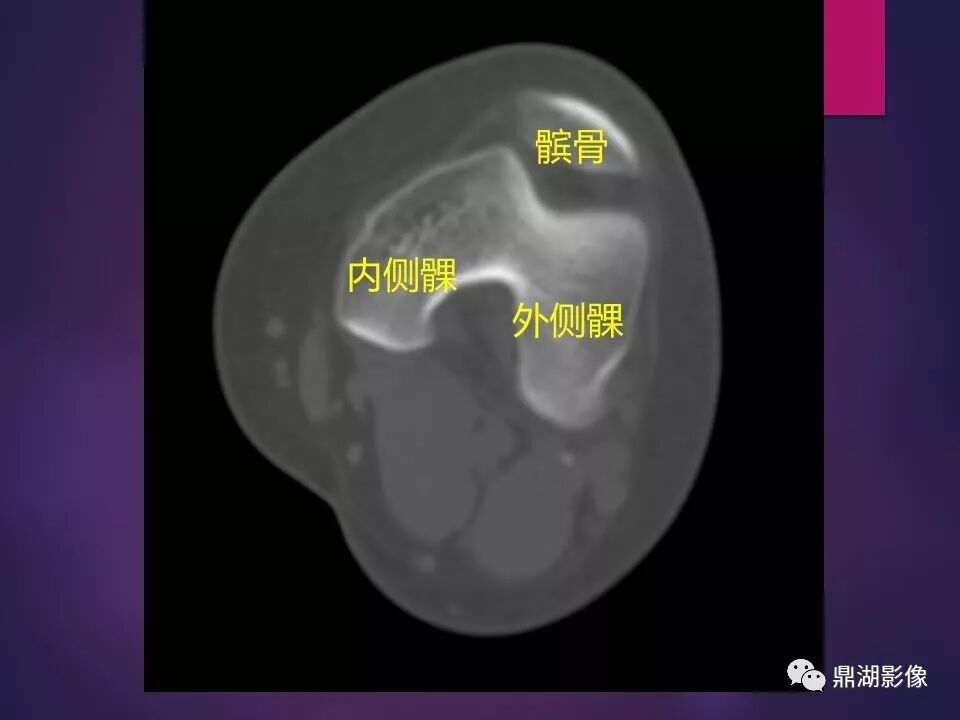

来源于:鼎湖影像 贵阳医学院医学影像系